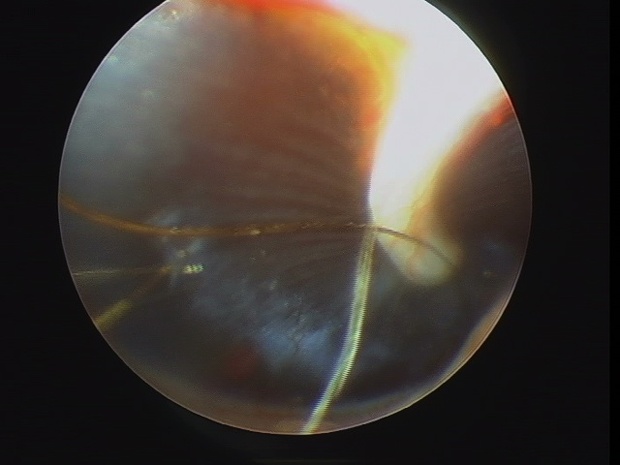

膀胱鏡

雌の場合は、尿道から直接膀胱にカメラを入れて、膀胱や尿道内を観察することができます(犬の大きさによってはできない場合もあります)。膀胱の中のしこりなどが見つかった場合、原因不明の膀胱炎が続く場合、腹腔鏡(膀胱鏡)で膀胱内の観察や生検が可能になります。